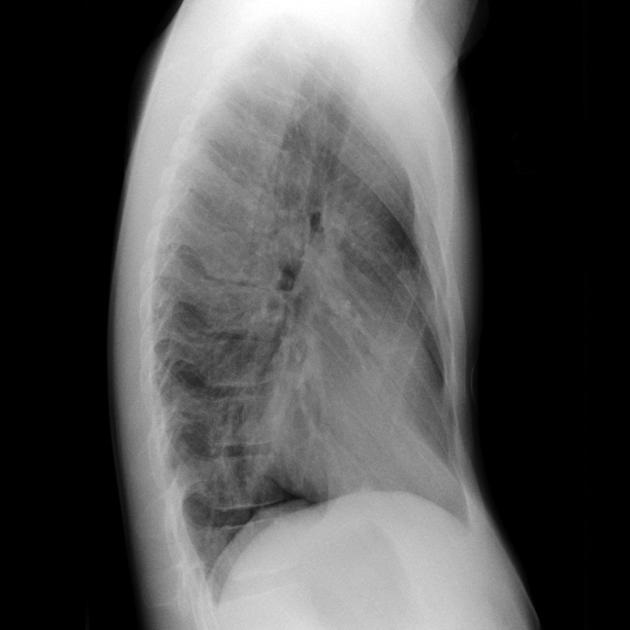

Image radiologique de cliche1

de face AP d'une syndrome de Poland avec aplasia dui

muscle pectoralis droit . Aspect de hyperluscence du

poumon droit est très net |

Cliche de face PA d'une

syndrome de Poland avec de hypolasia du muscle

pectoralis majeur droit . Ce qui donne une aspect

radiologique est hyperluscence du 1/2 superieure du

champ pulmonaire droit |